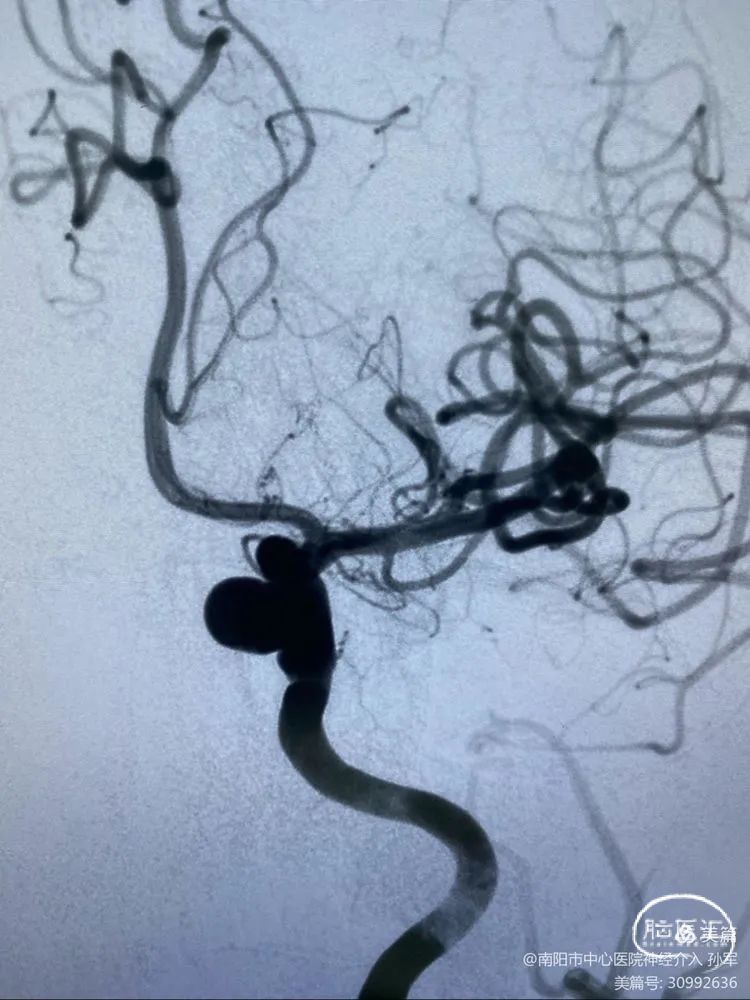

3

随着支架的释放,支架远端导丝移动到大脑中动脉分支。

4

经过调整,支架远端导丝竟然刺向豆纹动脉,且难以摆脱,考虑到支架释放后支架导丝还要前行很远,一旦刺破豆纹动脉将会导致灾难性后果。